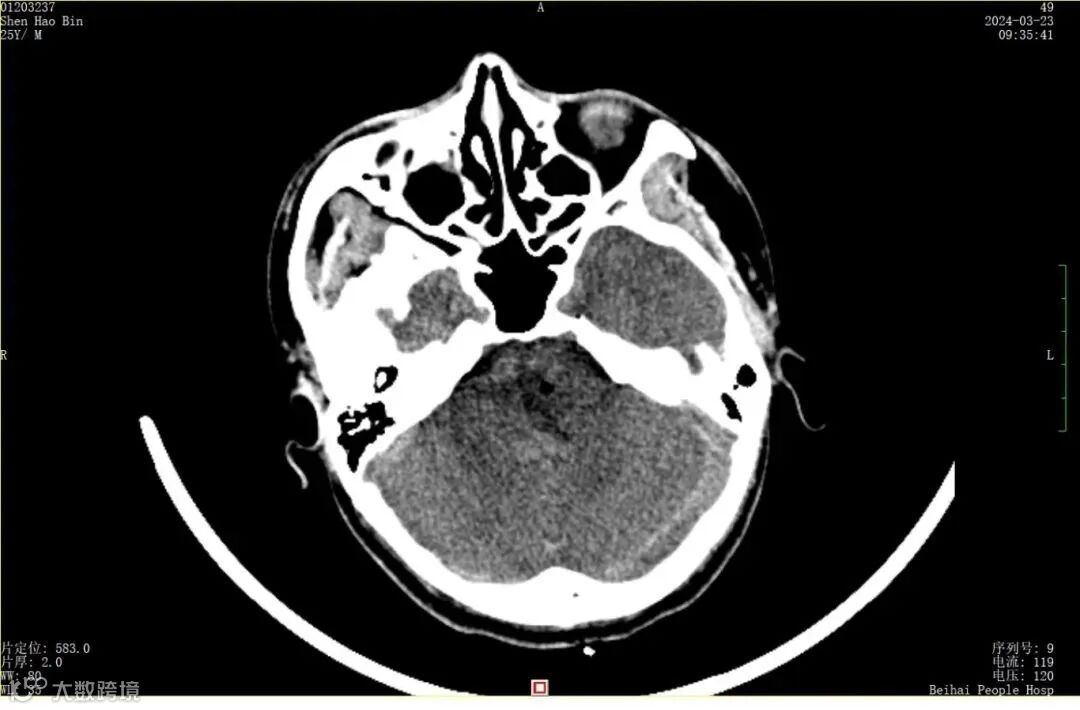

北海25岁男青年头痛5天,检查原来是脑出血